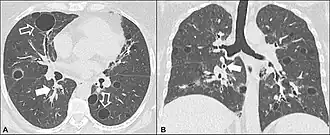

- КТ высокого разрешения, на которой выявляют утолщение межальвеолярных перегородок, центролобулярные узелки, кистозные полости и небольшие участки консолидации легочной ткани. Для КТ картины характерны участки пониженной прозрачности паренхимы по типу «матового стекла».